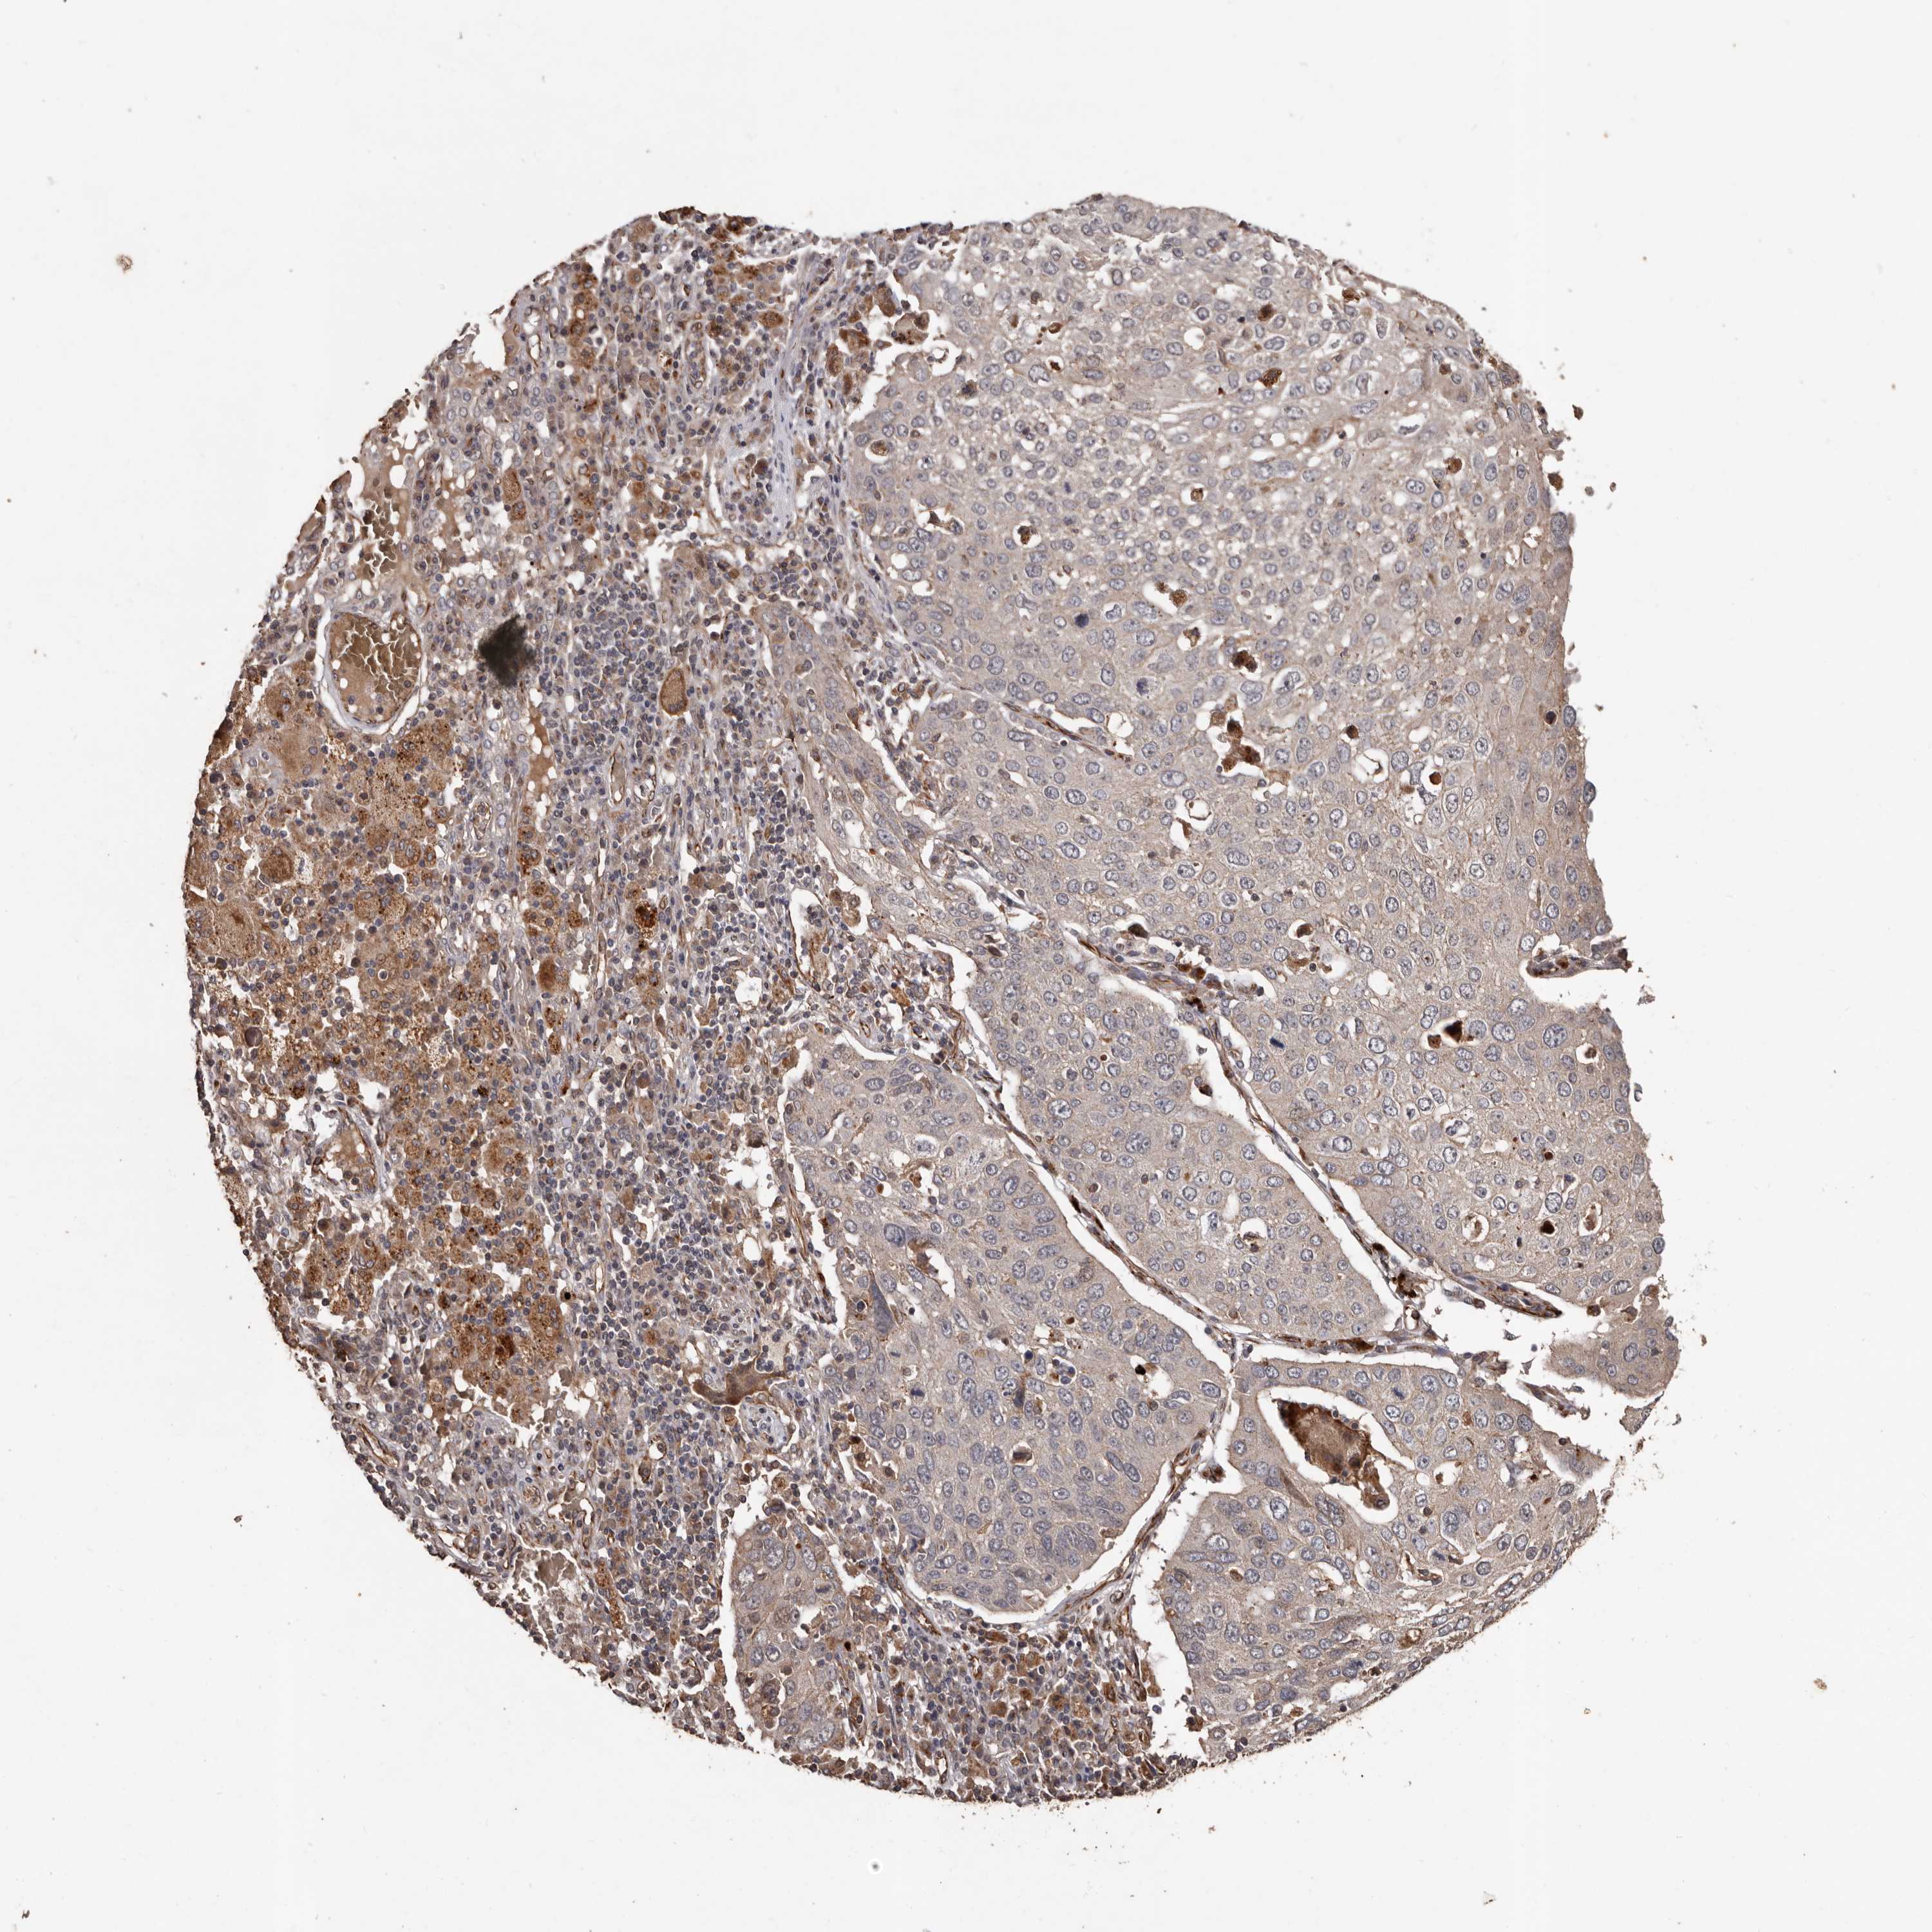

LUNG SQUAMOUS CELL CARCINOMA (TCGA) - Interactive survival scatter ploti

The Survival Scatter plot shows the clinical status (i.e. dead or alive) for all individuals in the patient cohort, based on the same data that underlies the corresponding Kaplan-Meier plots. Patients that are alive at last time for follow-up are shown in blue and patients who have died during the study are shown in red.

The x-axis shows the expression levels (FPKM) of the investigated gene in the tumor tissue at the time of diagnosis. The y-axis shows the follow-up time after diagnosis (years). Both axes are complimented with kernel density curves demonstrating the data density over the axes. The top density plot shows the expression levels (FPKM) distribution among dead (red) and alive patients (blue). The right density plot shows the data density of the survived years of dead patients with high and low expression levels respectively, stratified using the cutoff indicated by the vertical dashed line through the Survival Scatter plot. This cutoff is automatically defined based on the FPKM cutoff that minimizes the p-score. The cutoff can be changed by dragging the vertical line or by entering a cutoff value in the square labeled "Current cut-off".

Under the Survival Scatter plot the p-score landscape (black curve; left axis) is shown together with dead median separation (red curve; right axis). Dead median separation is the difference in median mRNA expression between patients who have died with high and low expression, respectively. It is calculated as follows: median FPKM expression of dead patients with high expression - median FPKM expression of dead patients with low expression. This is intended to aid the user in visually exploring custom cutoffs and the associated p-scores and dead median separation.

Individual patient data is displayed and can be filtered by clicking on one or more of the category buttons on the top of the page. Categories describing expression level and patient information include: high, low, alive, dead, female, male and tumor stages. The scale of the x-axis can be toggled between linear and log-scale by clicking on the "x log" button. Mouse-over function shows TCGA ID, patient information and mRNA expression (FPKM) for each patient.

& Survival analysisi

Kaplan-Meier plots summarize results from analysis of correlation between mRNA expression level and patient survival. Patients were divided based on level of expression into one of the two groups "low" (under cut off) or "high" (over cut off). X-axis shows time for survival (years) and y-axis shows the probability of survival, where 1.0 corresponds to 100 percent.

BRAT1 is not prognostic in Lung Squamous Cell Carcinoma (TCGA)

Best expression cut offi

Based on the FPKM value of each gene, patients were classified into two groups and association between prognosis (survival) and gene expression (FPKM) was examined. The best expression cut-off refers the FPKM value that yields maximal difference with regard to survival between the two groups at the lowest log-rank P-value. Best expression cut-off was selected based on survival analysis .

When clicking on this number, the vertical dashed line indicating cut-off, the interactive survival plot, and the Kaplan-Meier curve will be adjusted to show results based on the best expression cut-off.

: 20.47

P scorei

Log-rank P value for Kaplan-Meier plot showing results from analysis of correlation between mRNA expression level and patient survival.

N/A

TCGA RNA samplesi

RNA-seq data is reported as average FPKM (number Fragments Per Kilobase of exon per Million reads), generated by the The Cancer Genome Atlas (TCGA) .

Normal distribution across the dataset is visualized with box plots, shown as median and 25th and 75th percentiles. Points are displayed as outliers if they are above or below 1.5 times the interquartile range. FPKM values of the individual samples are presented next to the box plot.

Average pTPM 25.4

Number of samples 489